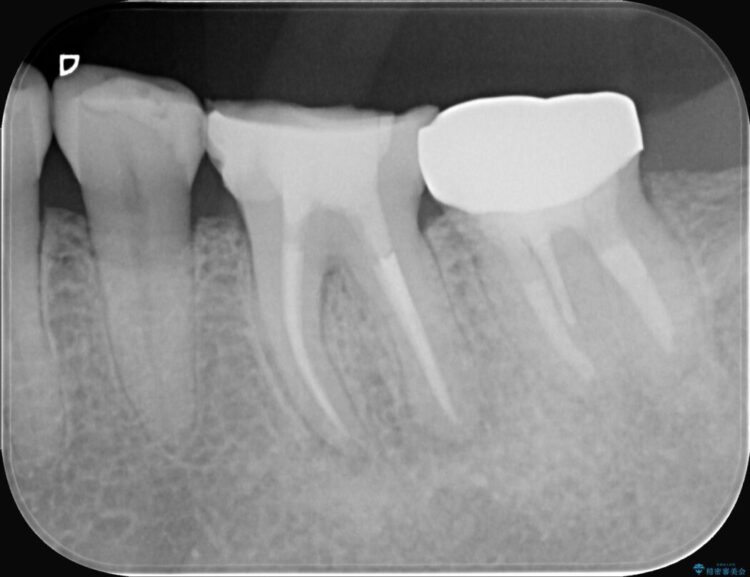

治療後について

今回の治療は、特に難易度の高い石灰化した根管が対象でした。

まず、治療中の細菌感染を防ぐためにラバーダムを使用。次に、歯科用顕微鏡で治療部位を何十倍にも拡大しながら、狭窄した根管の入り口を探し、慎重に拡大・清掃を行いました。顕微鏡を用いることで、肉眼では不可能だった根管内部の細かい構造を確認しながら、感染源を徹底的に除去することができました。これにより、難症例の奥歯でも再発リスクを抑えた適切な処置を行うことができ、治療後に痛みは解消。大切な歯を長期間にわたり保存することができました。